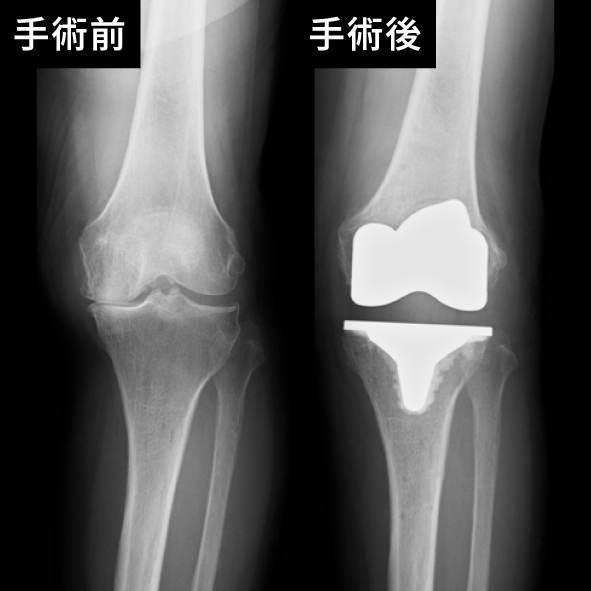

膝関節の手術前後

手術の種類には、関節全体を置き換える「全人工関節置換術」と、一部のみを置き換える「部分人工関節置換術」があり、患者さまの症状や状態に応じて選択されます。当院では、専門医が最新の技術を駆使して安全で精密な手術を行い、術後の回復を最大限にサポートします。